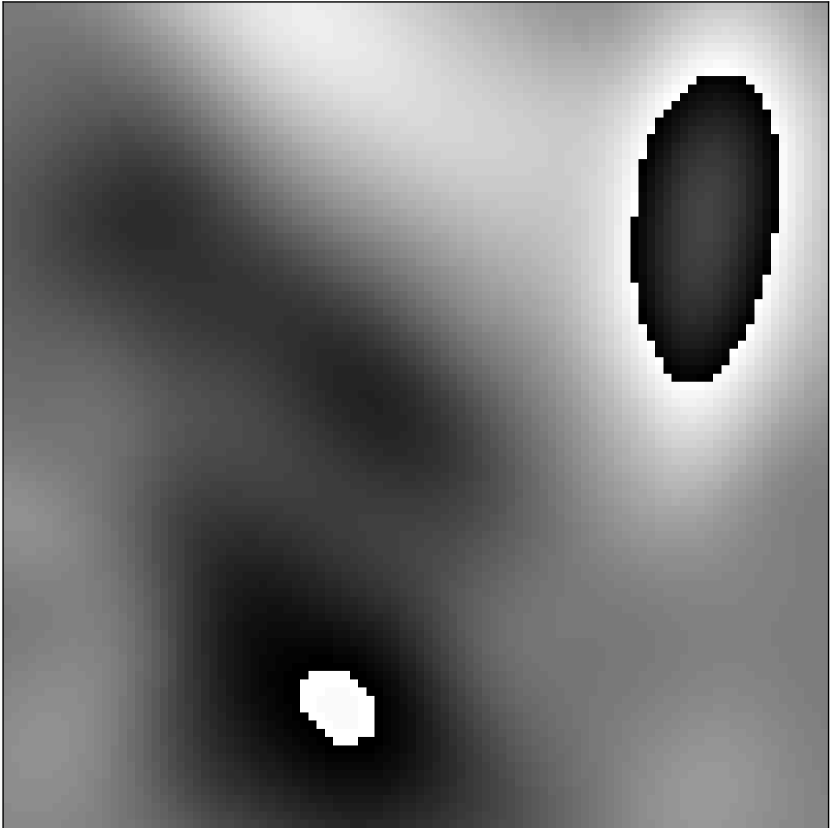

2.2.1 Simulation

The simplest Gibbs simulation could be accomplished by cropping the k-space representation of a high-resolution image. However, in practice MR acquisitions are affected by many factors other than the Gibbs phenomenon. We simulate a subset of these effects. Figure 1 shows a flowchart of the simulation pipeline. The simulation begins with raw grayscale ImageNet image (converted via BT.601 color standards), resized to a standard size of using bilinear interpolation [30]. The simulation then randomly flips and/or transposes the image, each with a 50% probability. After flipping and transposing, the simulation proceeds to the random phase step. The random phase simulation generates a random set of Gaussian radial basis functions for each simulated image - this is described in detail in Appendix A. An example of simulated phase compared to a true in vivo phase case is shown in Figure 3.

Simulated Phase

In Vivo Phase

Phase Angle (Radians)

The random phase simulation requires a number of probabilistic parameters for specifying the distribution of the simulated phase - these are reported in the appendix.

When and are not too large, will typically be smooth as in real application settings; however, sharp changes can also occur during training when basis function centers are near each other. As a further form of data augmentation, we include a 1% probability that no phase at all is simulated. Figure 3 shows an example of simulated phase compared to real phase from in vivo data. For our experiments, we used , , , , and . We set and to restrict the center of the Gaussian basis function to the image support in the th dimension.